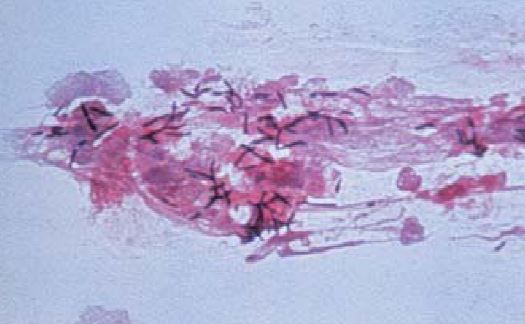

مستعمرات النوع البكتيري C. diphtheria بصبغة جرام

خلايا هذا النوع البكتيري هوائية وغير هوائية اختيارياً facultative anaerobs ولها القدرة على النمو في درجات حرارة ما بين 40-20 درجة مئوية وتعتبر درجة الحرارة 37 هي المثلى ، وهي موجبة لصبغة جرام وغالباً ما يكون الصبغ غير تساوي وباهت، كما أنها متعددة الأشكال والأطوال فتكون أحياناً عصوية وعلى هيئة مضرب الكرة club shape تتواجد في تجمعات ملتصقة بزوايا مختلفة بما يشبه الحروف الصينية . عند صبغتها بصبغة Neisser تظهر أجسام على الأقطاب (وهي عبارة عن عديد الفوسفات مخزنة في أحد الأقطاب). هناك 4 أنواع حيوية biovars وهم gravis وintermedius و mitis وكذلك belganti . وهذه الأسماء تستعمل لوصف شدة الإصابة ويتواجد هذا النوع البكتيري كفلورا طبيعية للقناة التنفسية العلوية والجلد.